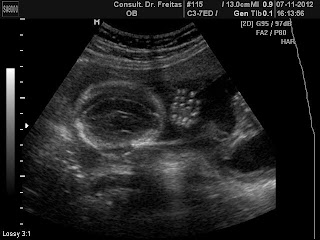

ultrassom 11 semanas e 4 dias.